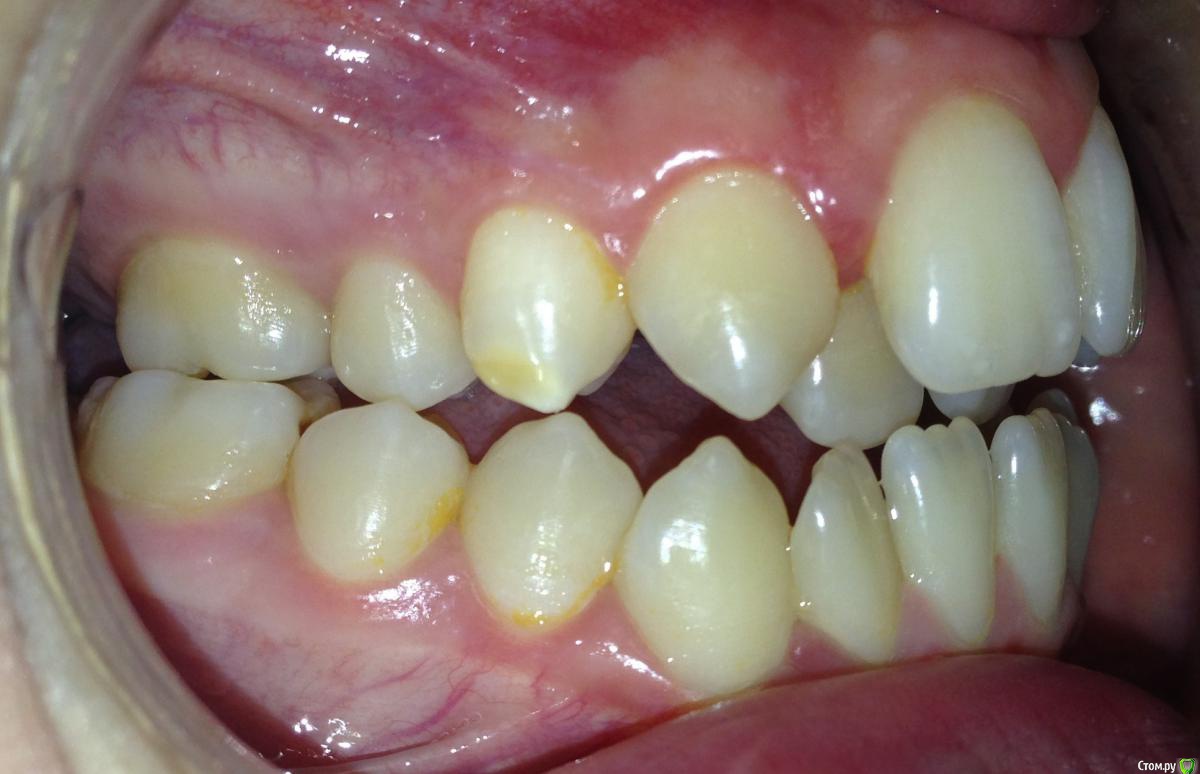

Алевтина Петровна Опубликовано 26 августа, 2015 Поделиться Опубликовано 26 августа, 2015 Всем добрый вечер. Я начинающий ортодонт. Надеюсь,что вы поможете с планом лечения. Пришел пациент. 13 лет. Ситуация по мне непростая, но очень интересная. Ссылка на комментарий

Алевтина Петровна Опубликовано 26 августа, 2015 Автор Поделиться Опубликовано 26 августа, 2015 Прикрепляю дополнительные фото, извините за качество. Это моя первая публикация, пытаюсь разобраться. Ссылка на комментарий